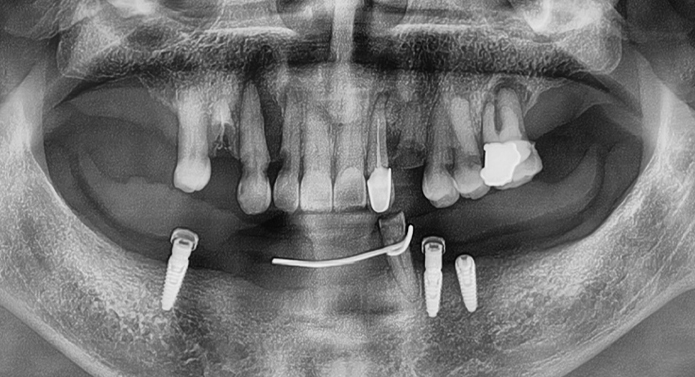

흔들리는 임플란트를 새로 식립하고 필요에 따라 뼈이식을 진행합니다.

염증 치료 및 뼈이식 수술을 통한 잇몸뼈 보강합니다.

교합과 심미성을 고려하여 새로운 보철물 수복합니다.

문제가 생긴 보철물(크라운·브릿지 등)만 정밀하게 제거하고

새롭게 제작·장착하는 고난도 치료입니다.

단순한 탈락이나 파절이 아닌 교합력 문제,

지대주 헐거움, 잇몸 염증 등

다양한 원인을 정확히 분석하고 교정하는 것이 핵심입니다.

※ 결국 임플란트를 다시 심어야 하는 상황까지 발생할 수 있습니다.